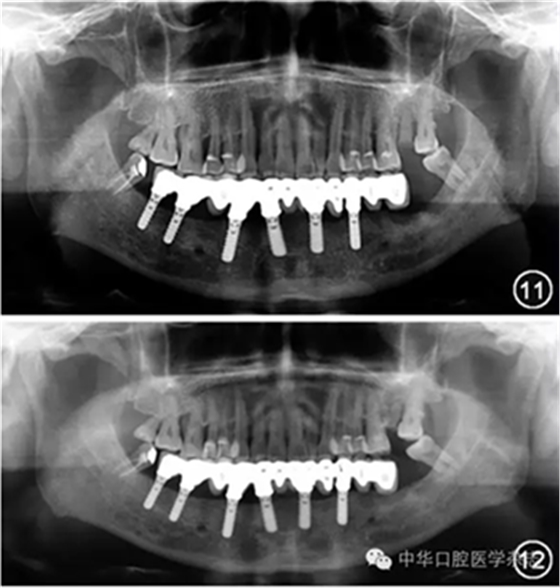

即刻種植后,常規(guī)的治療方案是在永久修復(fù)體戴入前采用臨時活動義齒修復(fù)作為過渡(圖5~12)。近年來,隨著種植體表面處理方法的改良以及種植外科與修復(fù)技術(shù)的進(jìn)步,即刻種植后即刻修復(fù)或即刻負(fù)載在臨床上的應(yīng)用取得了成功。系統(tǒng)性回顧在2年的觀察期內(nèi),即刻種植即刻負(fù)載與常規(guī)負(fù)載的種植體存留率分別為98.2% 和98.5%,兩組差異無統(tǒng)計學(xué)意義。需要指出的是,在多數(shù)報告即刻種植即刻負(fù)載的研究中,修復(fù)體并沒有正中咬合接觸和側(cè)方咬合接觸,種植體的微動明顯減少。